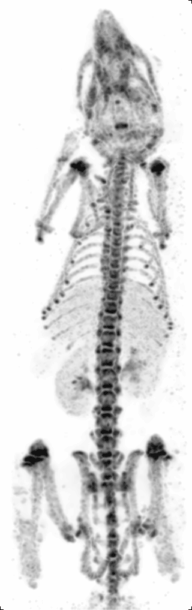

Principle: Similar to PET, Single Photon Emission Computed Tomography (SPECT) also images living systems through γ-rays emitted from within the subject. Unlike PET, the radioisotopes used in SPECT (such as technetium-99m) emit γ-rays directly,[10] instead of from annihilation events of a positron and electron. These rays are then captured by a γ-camera rotated around the subject and subsequently rendered into images.

Strengths: The benefit of this approach is that the nuclearisotopes are much more readily available, cheaper, and have longer half-lives as compared to micro-PET isotopes. Like micro-PET, micro-SPECT also has very good sensitivity and only nanograms of molecular probes are needed.[15] Furthermore, by using different energy radioisotopes conjugated to different molecular targets, micro-SPECT has the advantage over micro-PET in being able to image several molecular events simultaneously. At the same time, unlike micro-PET, micro-SPECT can reach very high spatial resolution by exploring pinhole collimation principle (Beekman et al.) [16] In this approach, by placing the object (e.g. rodent) close to the aperture of the pinhole, one can reach high magnification of its projection on detector surface and effectively compensate for intrinsic resolution of the crystal.

Weaknesses: Micro-SPECT still has considerable radiation which may affect physiological and immunological pathways in the small animals. Also, radiation may affect tumor size in cancer models as it mimics radiotherapy, and thus extra control groups might be needed to account for this potential confounding variable. Micro-SPECT can also be up to two orders of magnitude less sensitive than PET.[2] Furthermore, labeling compounds with micro-SPECT isotopes require chelating molarities which may alter their biochemical or physical properties.

Cancer research: Micro-SPECT is often used in cancer research for molecular imaging of cancer-specific ligands. It can also be used to image the brain because of its penetration power. Since newer radioisotopes involve nanoparticles such as 99mTC-labelled iron oxide nanoparticles, they could potentially be combined with drug delivery systems in the future.[14]